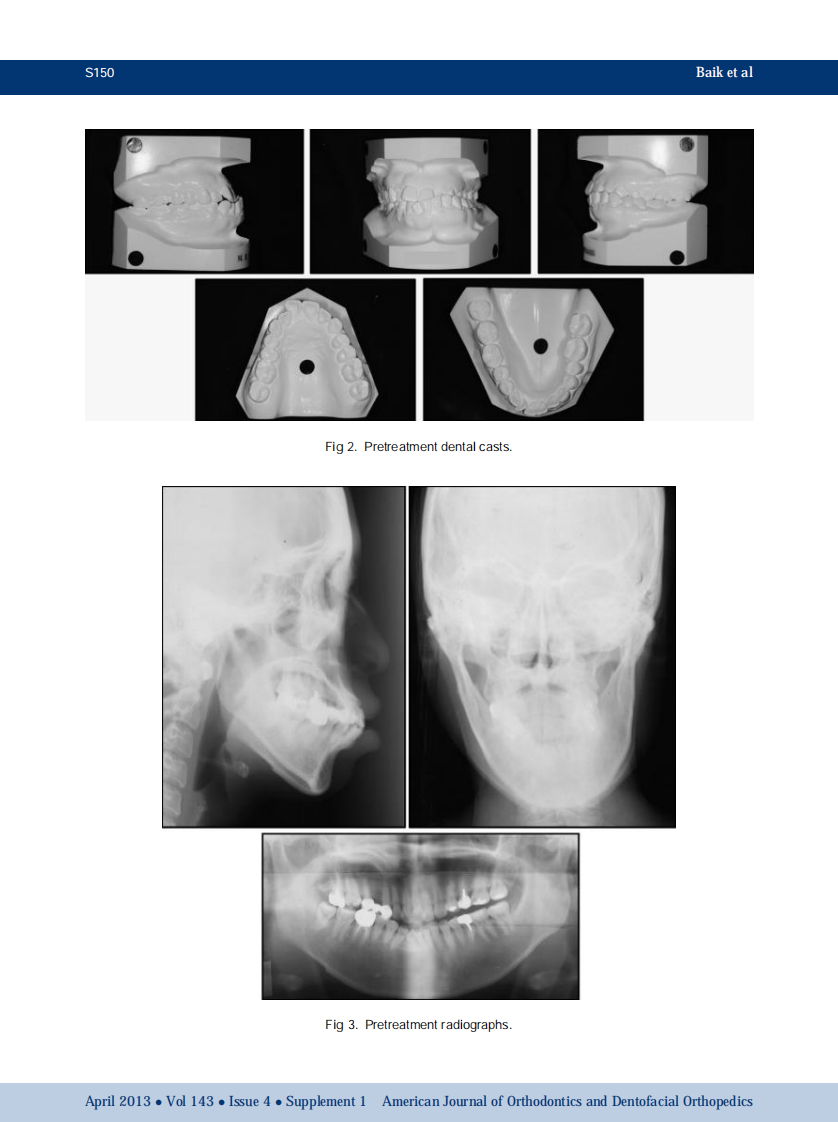

1-s2.0-S0889540612009006-main.pdf